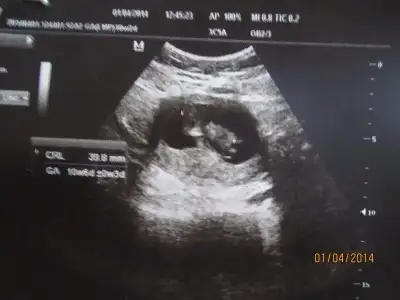

ya kızlar benim iki hafata önceki ultrasonum var belli midir? dr erkek muhtemelen dedi ama kesin demedi. yeni ultrasonu ekleyemedim bir türlü ışık patlaması oluyor. çocuğun kafası kocaman görüyodu korktum ya siiznkilerde de öyle oldu mu? kötü bişey olsa dr söylerdi dimi? ya da ultrasn eski diye mi öyle çıktı?

Eki Görüntüle 1047942

Eki Görüntüle 1047943